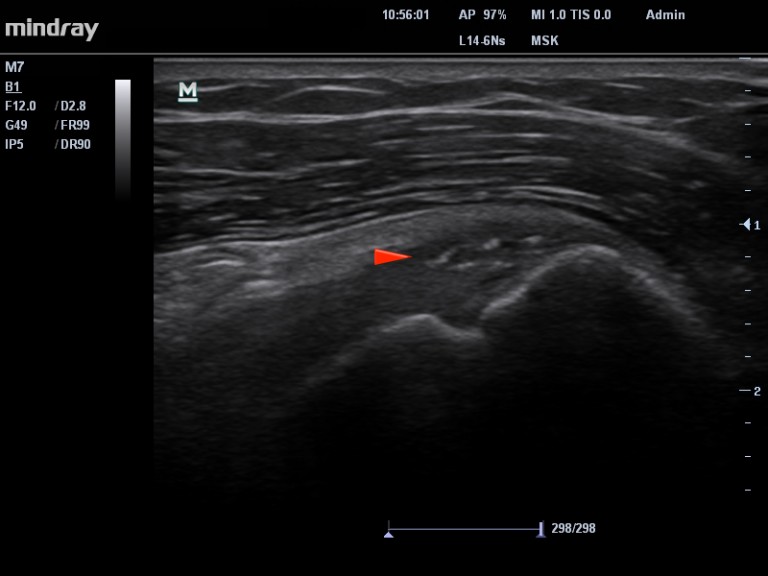

Le dépôt calcique libère des cristaux dans les tissus avoisinants. Cette libération soudaine, va générer une inflammation telle que le patient se présente avec une épaule « gelée » par la douleur, aussi appelée l’épaule calcifiante aigue. Dans l’immense majorité des cas, la phase inflammatoire s’estompe en une dizaine de jours et le patient devient asymptomatique (Images 3 et 4 ) . Aucun traitement n’est habituellement nécessaire. Cependant en cas de douleur importante, insomniante, on peut recommander au patient  une infiltration de la bourse sous acromio-sous deltoidienne.

Image 3. Calcification en phase de résorption. La patiente consulte pour une douleur importante à l’épaule.